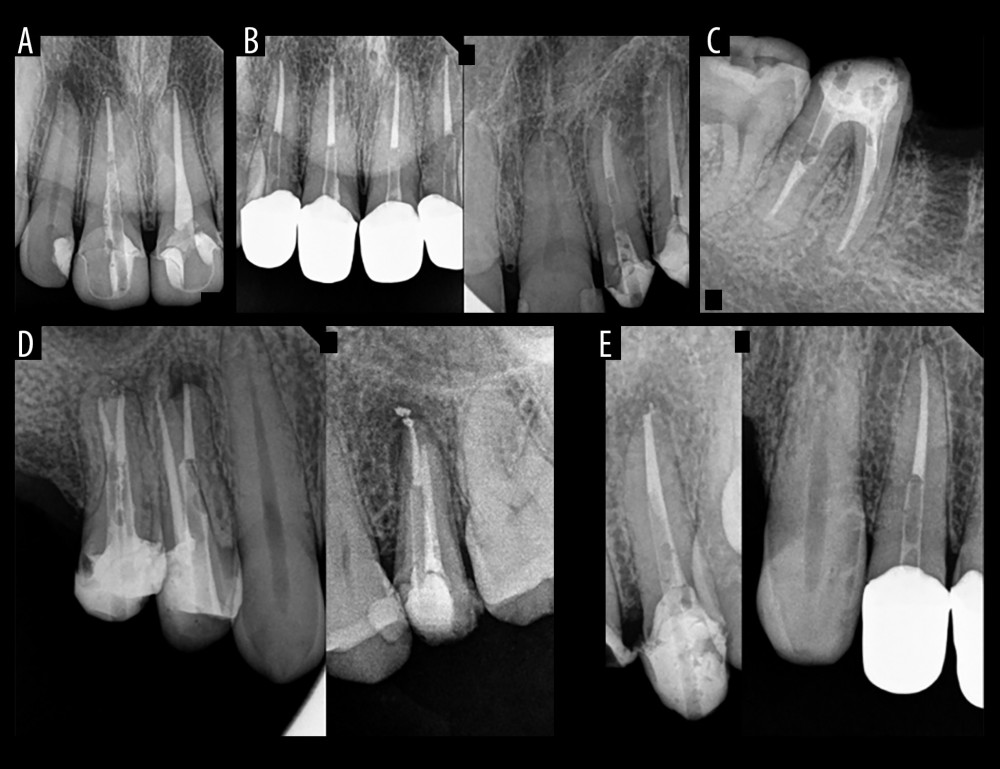

Medical Science Monitor Radiographic Assessment of 121 Glass Fiber

Medicina Free FullText Radiographic Evaluation of the Gap between Fiber Post Radiograph intraradicular posts are useful adjuncts in the restoration of endodontically treated teeth. fibrekleer 4x fiber posts feature outstanding radiopacity of up to 400% of aluminum to help ensure that they are instantaneously. Radiograph of typical fiber post when prepared for a. radiopaque translucent fiber post system. Designed for use with the prosystem gt® and gt® series x®. Fiber Post Radiograph.

The periapical radiography of 21 numbered tooth following fiber post Fiber Post Radiograph radiopaque translucent fiber post system. Radiograph of typical fiber post when prepared for a. Designed for use with the prosystem gt® and gt® series x® complete endodontic. intraradicular posts are useful adjuncts in the restoration of endodontically treated teeth. fibrekleer 4x fiber posts feature outstanding radiopacity of up to 400% of aluminum to help ensure that they. Fiber Post Radiograph.